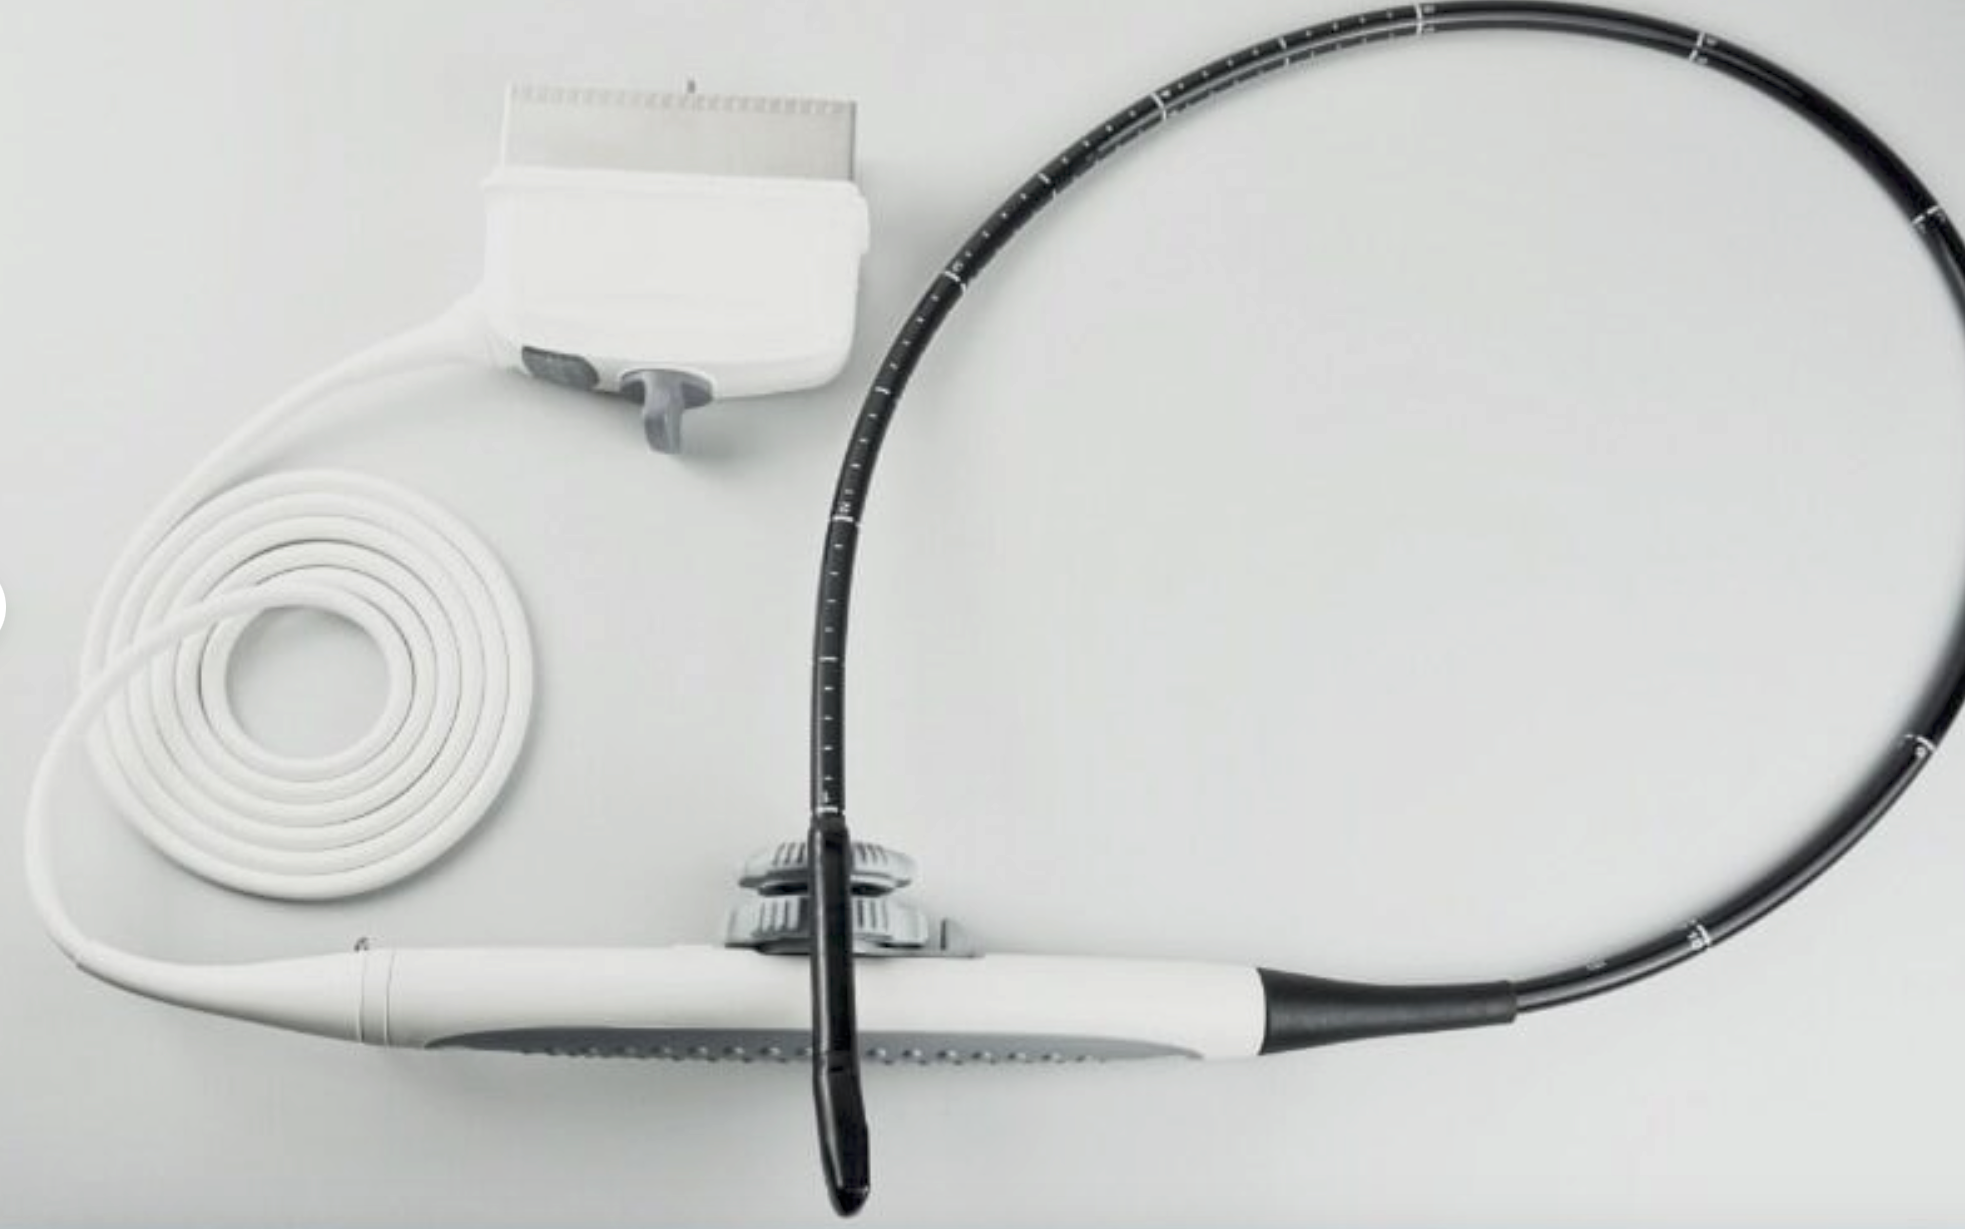

Toshiba PVF-381MT 3.75 MHz Ultrasound Probe

Sale price$ 1,799.06